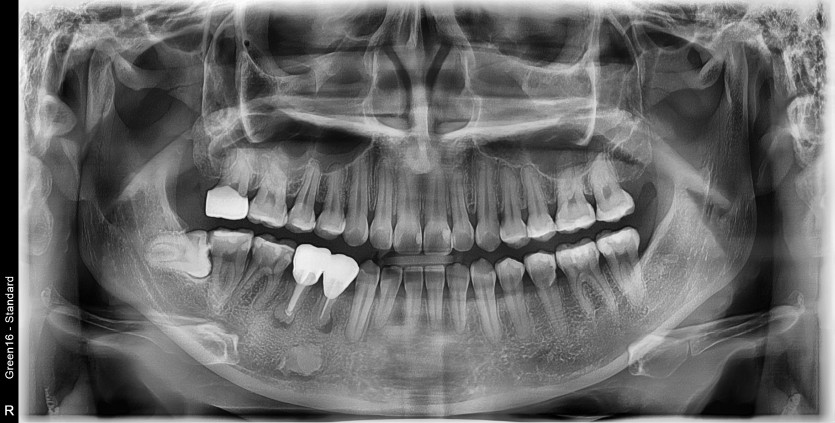

#48 사랑니 발치

구강 외과 전문의가 당일 발치했습니다.